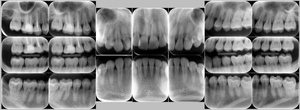

症例4

before

症例

after

抜歯前

抜歯後

基本情報

年齢・性別 26歳・男性

主訴 主訴:左下親知らず痛い

治療部位:左下8番

治療内容 ・左下8番埋伏抜歯

〈歯周病治療〉

①検査、資料取り(歯周ポケット検査、レントゲン14枚法、口腔内写真)、染めだし、歯磨き指導

②歯肉縁上の歯石除去、歯磨き指導、確認

③歯肉縁下の歯石除去(SRP)

④再評価

⑤メインテナンス

(2024年8月現在)

治療期間 約1ヶ月

治療費 合計:19,950円

〈内訳〉(全て保険診療3割負担)

①初診検査、左下8番埋伏抜歯:10,620円

②染めだし・歯磨き指導:1,110円

③歯磨き指導、確認・縁上歯石除去:2,830円

④縁下歯石除去(SRP)×2回:1,680円(×2回)

⑤再評価(歯周精密検査)・歯磨き指導:2,030円

リスク・副作用 ・歯石除去後、個人差はありますが1週間程度、歯を磨くといつもより出血することがあります。

・治療の結果、腫れていた歯ぐきが引き締まることで、歯ぐきが下がったように見えます。

下がった訳ではなく、本来の歯ぐきの位置に戻ったことによる見た目の変化です。

・歯ぐきが引き締まることにより、歯面が露出し知覚過敏の症状がでることがあります。

治療方針 左下の親知らずが痛いとのことでご来院された患者さまです。

親知らず周囲は汚れが落としきれておらず、歯ぐきが炎症を起こしている状態でした。

当日抜歯を希望されていたので、麻酔を効かせてから三次元的なレントゲン写真(CT)撮影し、抜歯を行いました。

その後、全顎的に歯石付着、歯ぐきの炎症が見られたので歯周病治療をその他の治療と並行して行っていきました。

特記事項 ・歯科受診約4年ぶり

・喫煙歴無し

・右下、左上の親知らずも抜歯済み

・コーヒー常飲

担当者所見 初診時は歯ブラシの交換時期を把握していなかった患者さまが歯ブラシを新しくしてから約1ヶ月後自分から歯ブラシを変えたことを教えてくださいました。

歯周病治療を進めていくうちに、患者さまの口腔内への意識が高まっていて治療が良い方向に進んでいきました。

歯周基本治療とセルフケアで歯ぐきの炎症や出血は初診時より大分改善されましたが、出血率を0%まで減らしていけるように今後は定期的な検診で歯ブラシの当て方や経過を患者さまと一緒に確認していこうと思います。